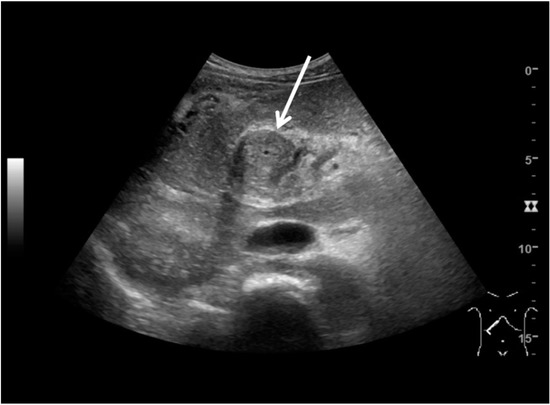

Abdominal ultrasound showed a large mass between the liver hilus and the pancreatic head (Figure 1), an enlarged spleen, and extensive collateral vessel formation. Contrast-enhanced computed tomography (CT) confirmed the presence of this mass with encasement of the hepatic arteries and common bile duct, dilation of the intrahepatic bile ducts, and portal vein thrombosis (Figure 2A,B). Due to the vascular encasement, the mass was deemed irresectable. An esophago-gastroduodenoscopy showed large esophageal varices. Elastography (FibroScan) showed only moderate (F2) liver fibrosis.

Figure 1. Ultrasound image of the abdominal mass (5.9 × 8.7 cm; arrow) in the right upper quadrant, surrounding the common bile duct.